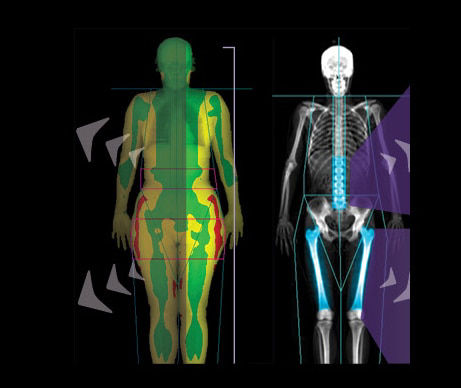

1. Color Mapping available on Lunar iDXA only.